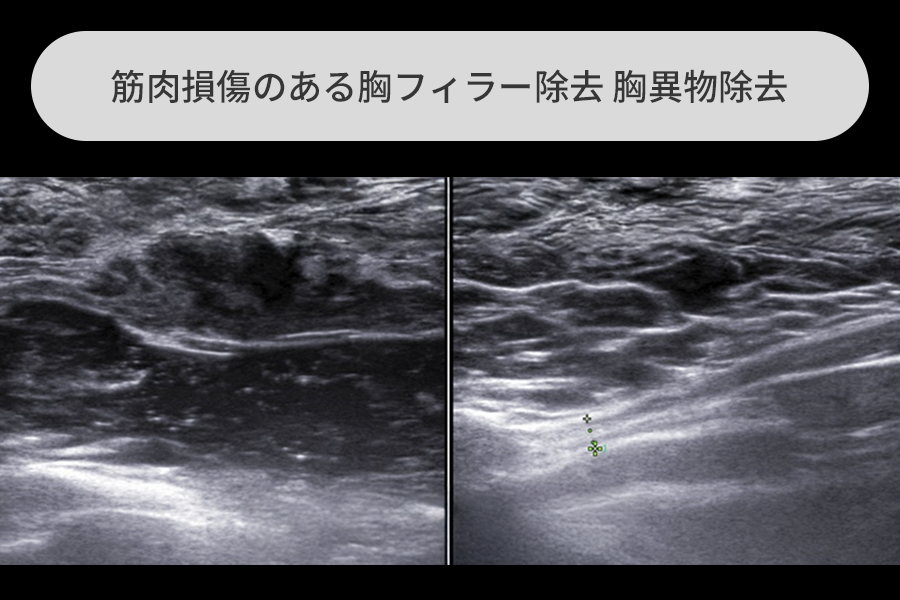

フィラー後に筋肉損傷により血が混じった乳頭分泌物が出た方

手術的フィラー除去の主な対象であるPAAGは体内で毒性を示しますが、特に筋組織の損傷が現れる場合、軽度ではフィラーの移動から、重度では炎症や血腫、筋組織の破裂まで様々な症状を見せます。

この方は血性乳頭分泌物のため乳がんを心配して来院されたケースで、

胸フィラー除去と損傷組織、血腫、裂けた筋肉組織を除去しました。